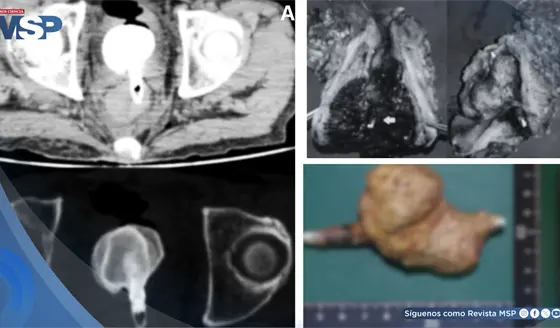

Hematuria reveló adenocarcinoma mucinoso de células en anillo de vejiga con metástasis pulmonar y ósea